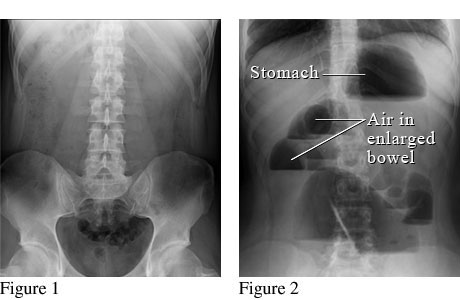

Abdominal X-ray of a bowel obstruction